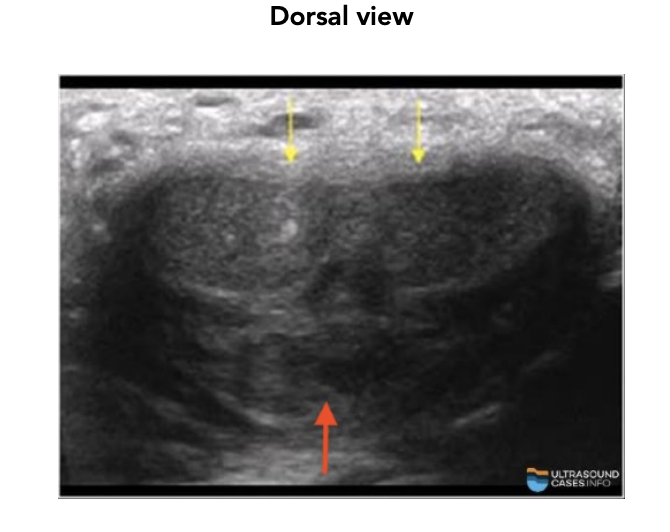

Two (dorsal side) (yellow arrows)

What does the corpus spongiosum contain?

urethra (red arrow)

Where is the corpus spongiosum located?

ventral side